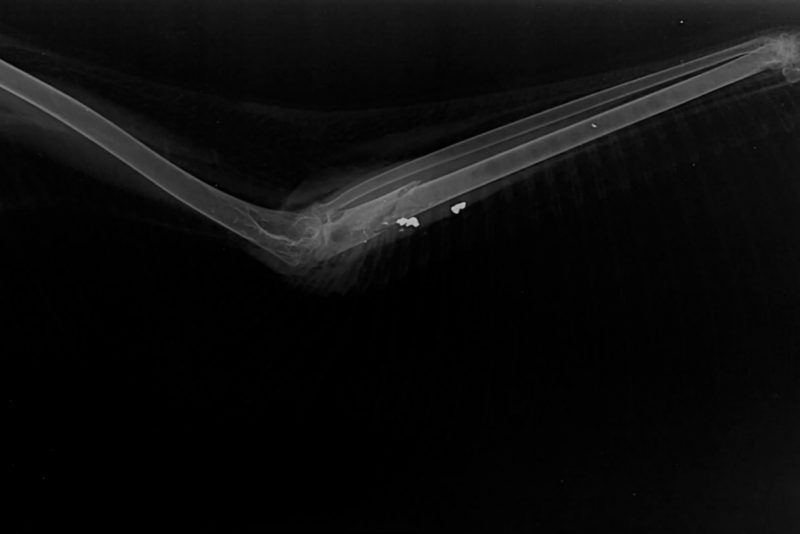

Após exame radiográfico, constatou-se a presença de um projétil de “chumbinho” alojado na asa direita do segundo animal. Além disso, o atobá também apresentava perda de musculatura, provavelmente causada por inanição (enfraquecimento extremo)  – Foto: Divulgação/R3 Animal/ND